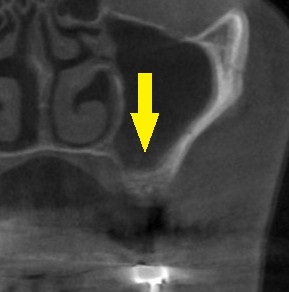

CTで見ると、通常の長さの10mm程のインプラントを埋入するには、やや骨の高さが不足していました。

そこで、ここは、ワイド径で長さの短いインプラントを用意して、患者様ご自身の骨を、上方の空洞に押し上げるようにドリリングすることで、人工骨を使用せずインプラント埋入を行なうこととしました。

下の写真、下段が手術後のCTです。